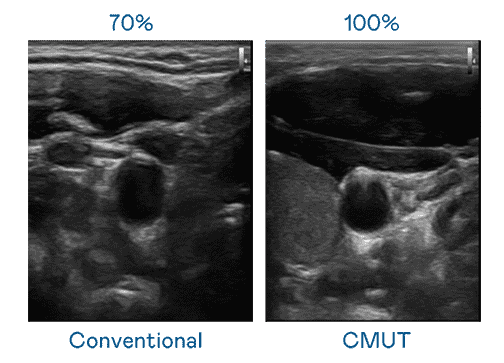

CMUT 技术是一种用电容式微机电元件来产生超音波讯号的技术。。与传统 PZT 压电式技术相比,,,,CMUT 频宽增加 30%,,,,更宽频的超音波讯号让影像解析度大幅提升,,是实现高影像品质医疗超音波扫描、、促进精准医疗发展的关键技术。。。

大频宽带来超清晰影像

超音波影像的解析度高低,,首先取决于探头能发出的讯号频宽。。。冰球突破 CMUT 可提供高清晰的超音波讯号,,,,提供高频宽、、高灵敏度、、影像纹理细节更高的超音波影像,,协助医护人员缩短影像判读时间及利用精准的医疗影像进行诊断。。。。